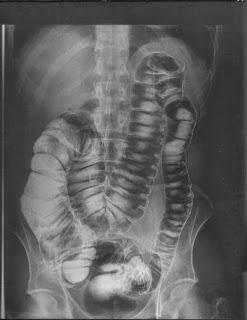

Megacólon

Megacólon adquirido é qualquer patologia que obstrui o conteúdo

intestinal e evita o movimento, resultando em distensão extrema do

cólon.